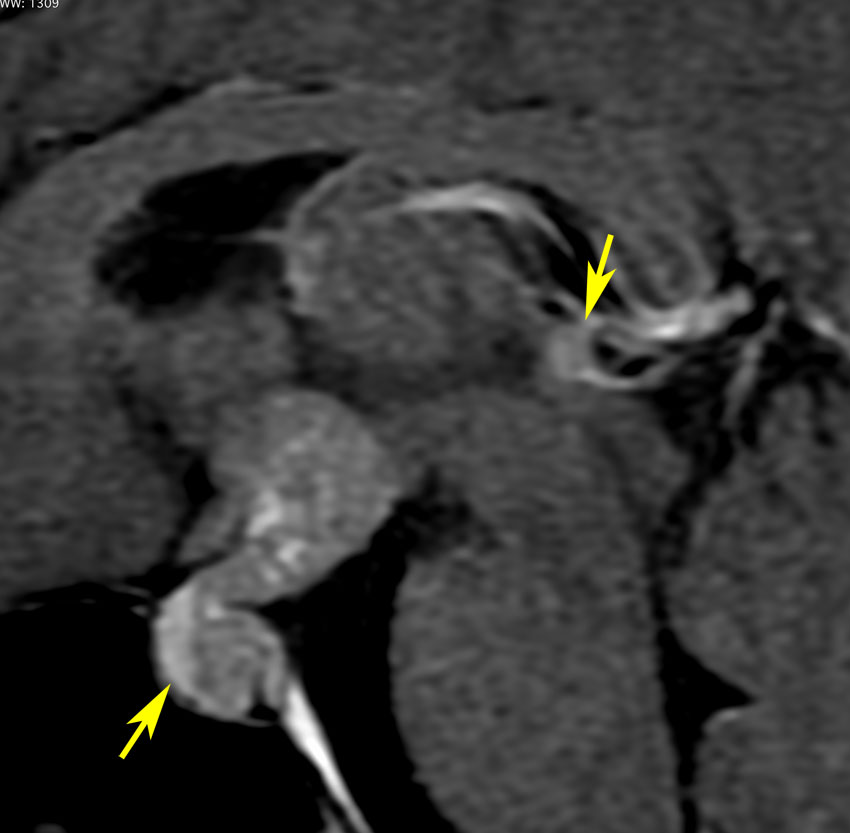

再発ジャーミノーマの画像です。延髄背側の閂 ovexという部位に再発しています。

このパターンはとても多いです。なぜかというと,全脳室照射の時に,第4脳室下端のovexの上衣 ependyum を照射野に入れない放射線治療医の先生がいるからです。放射線科の先生にもちょっとした知識が必要なのです。

これは再治療で腫瘍が消えても不可逆的な重症の延髄障害を残してしまいます。